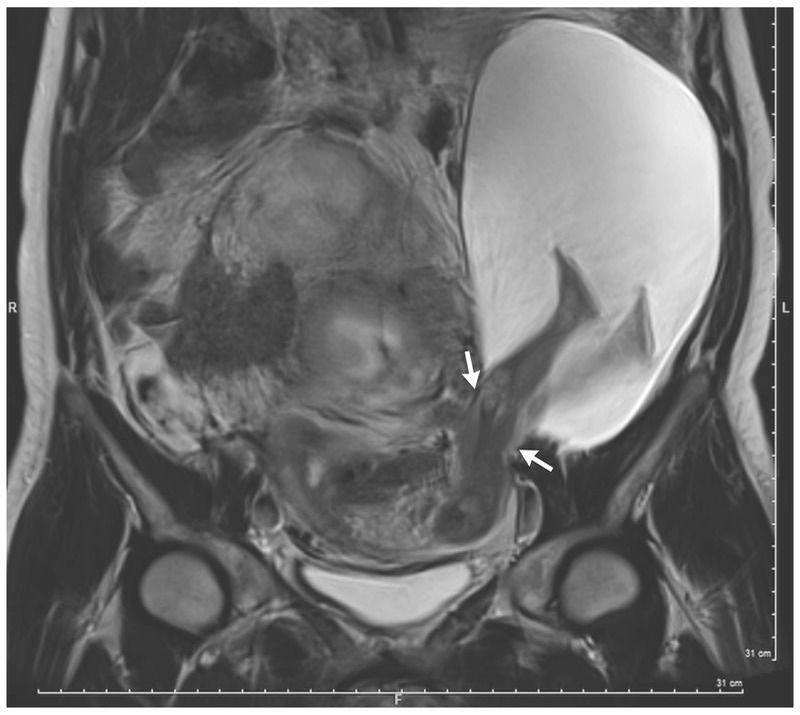

A 33-year-old asymptomatic woman (gravida 6, para 5) presented at 22 weeks of gestation with a large herniation of the amniotic sac through the left uterine wall that was detected by routine ultrasonography. She had had five previous cesarean sections through a transverse incision of the lower uterine segment and no previous vaginal deliveries. Magnetic resonance imaging revealed a 2.5-cm rupture of the left uterine wall (arrows) and a large amniocele that measured 19 cm by12 cm by 9 cm and contained fetal legs. The patient and her partner were informed of the potential risks of these findings, including complete uterine rupture, placenta accreta, hysterectomy, and preterm birth. They opted to proceed with the pregnancy with close monitoring. Repeat ultrasonography at 30 weeks of gestation revealed that the uterine dehiscence had extended 5 cm and the herniated sac had grown and included the fetal abdomen and legs. At 30 weeks of gestation, a healthy male newborn weighing 1385 g was delivered by cesarean section. After the delivery, the left posterior uterine rupture and large amniocele were identified and repaired. The patient had an uncomplicated postoperative course and was discharged from the hospital 5 days later. At 6 months of age, the baby was alive and well.